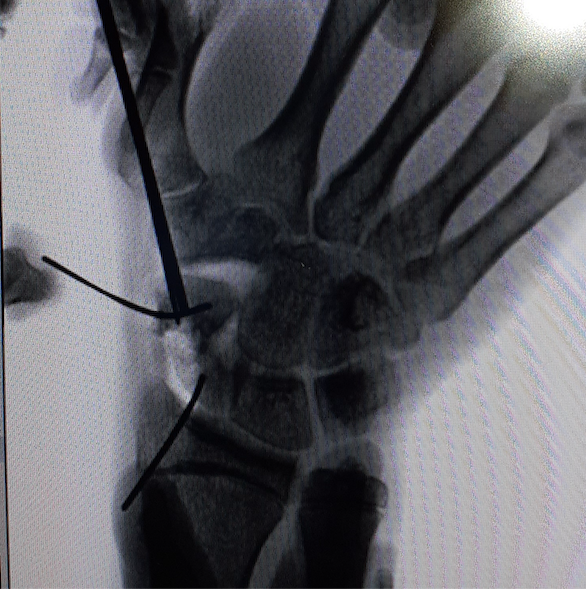

• Chirurgia della Mano e del Polso

La chirurgia della mano è una superspecializzazione che tratta patologie malformative, de...